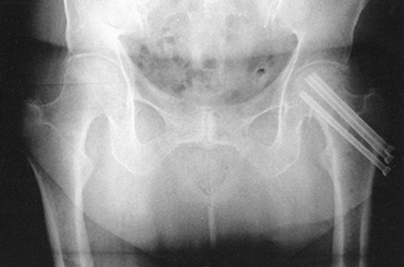

![]() |

|

Figure 11.22. A:

Comminuted proximal tibial fracture in an elderly patient, showing a combination of external and internal fixation to stabilize the comminuted periarticular fracture pattern in an osteopenic patient. B: Radiotranslucent carbon fiber rods facilitate assessment of the fracture site and proper timing of secondary intervention, yet provide sufficient stability to allow for soft-tissue consolidation. |